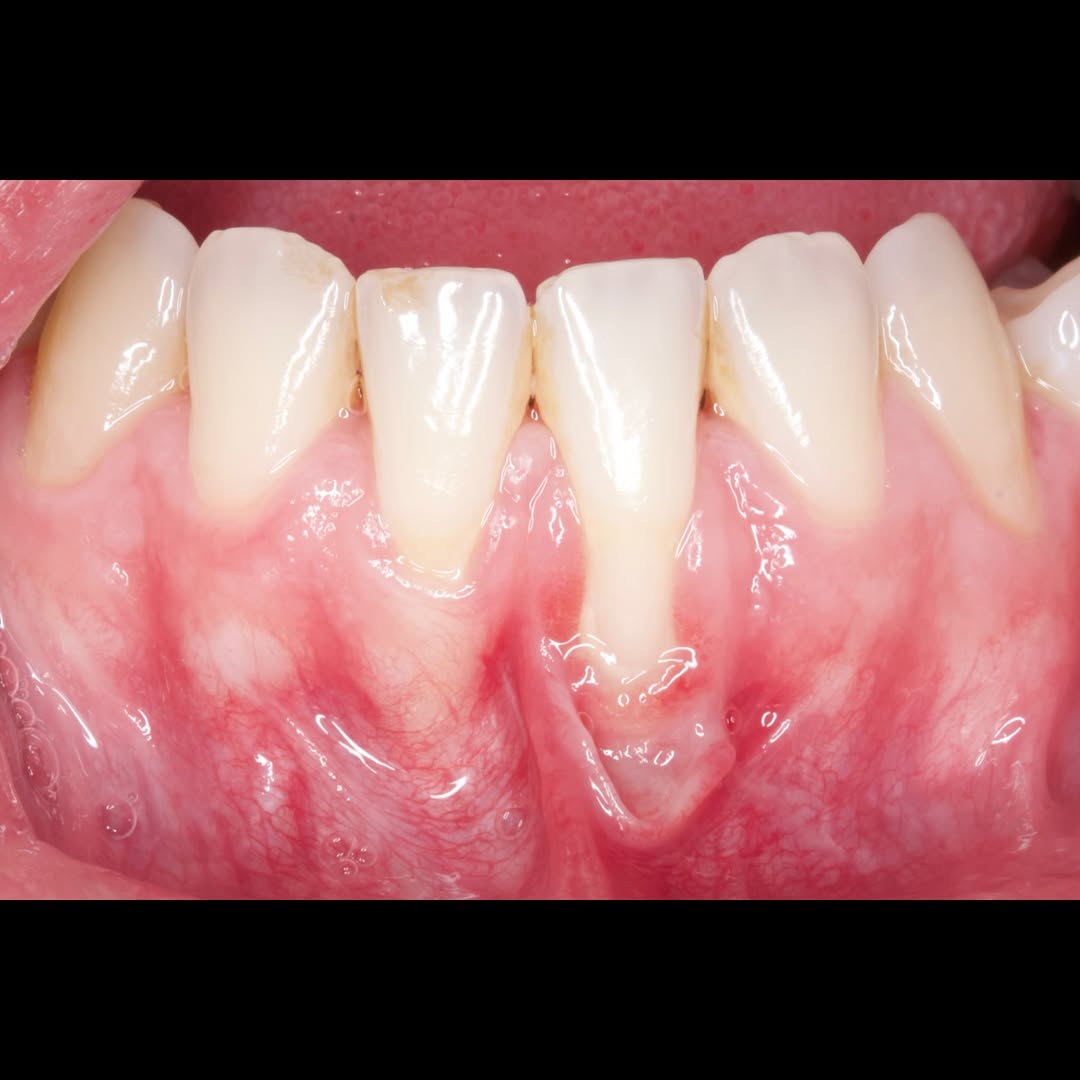

Durante una mañana, asistirás a una Cirugía Mucogingival de recubrimiento radicular de recesiones múltiples en IV y V sextante (36 a 43).

Aprende la planificación y técnica de la cirugía Mucogingival para el recubrimiento de recesiones y aumento de banda queratinizada en el sector anteroinferior

Durante una mañana, asistirás a una Cirugía Mucogingival de recubrimiento radicular de una recesión unitaria en 31 con frenillo asociado. Gracias al uso del microscopio y a la proyección en tiempo real en pantalla, verás exactamente lo mismo que veo yo durante la cirugía, sin tener que estar